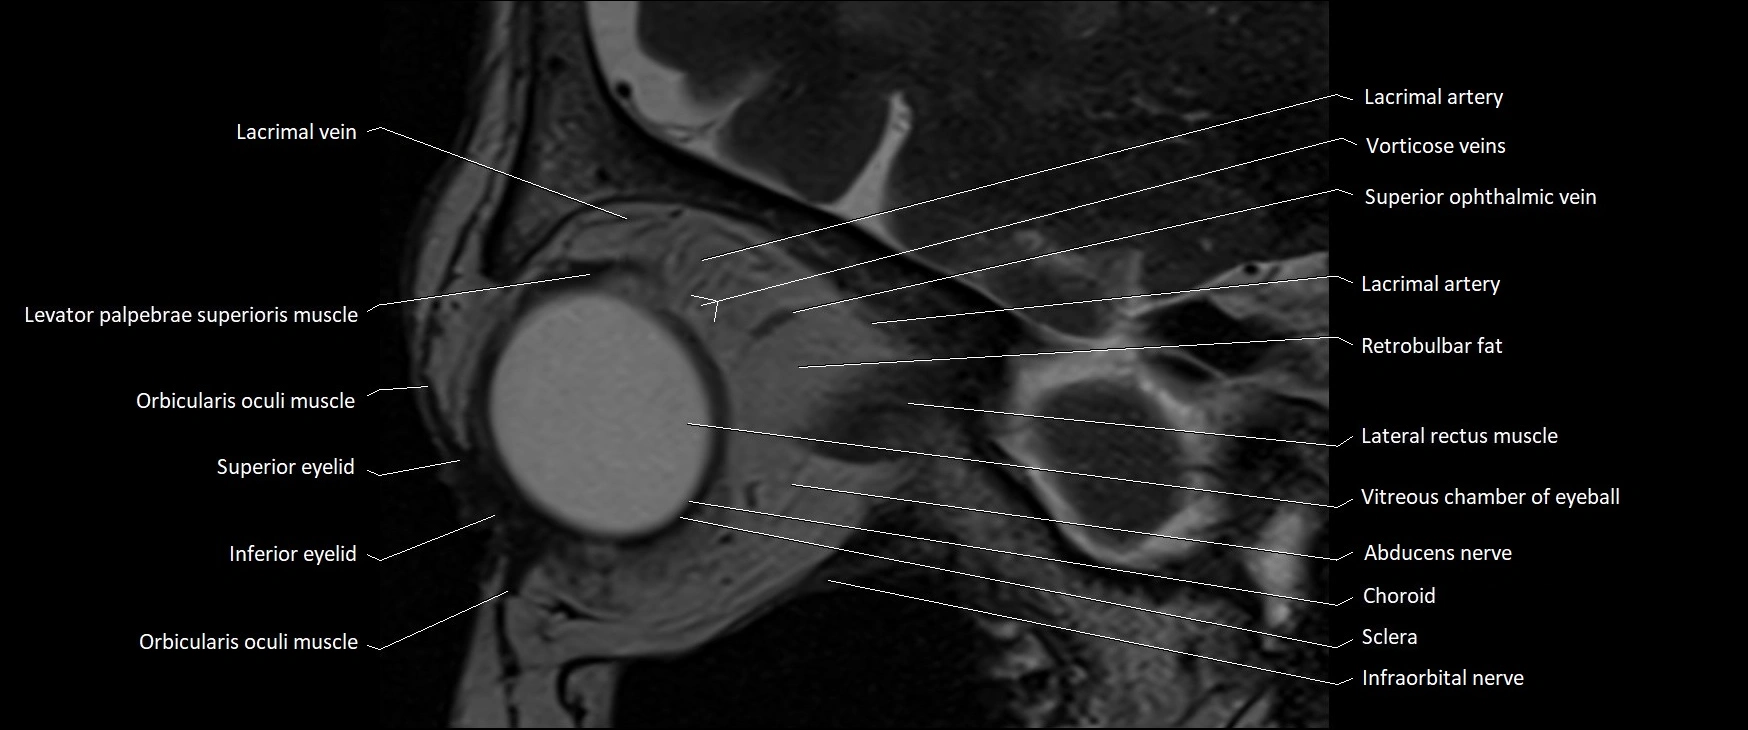

- Abducens nerve (Cranial nerve VI)

- Abducens nerve (orbital part )

- Choroid

- Inferior eyelid

- Inferior ophthalmic vein

- Infraorbital nerve

- Lacrimal artery

- Lacrimal vein

- Lateral rectus muscle

- Levator palpebrae superioris muscle

- Orbicularis oculi muscle

- Retrobulbar fat

- Sclera

- Superior eyelid

- Vitreous chamber of eyeball

MRI images